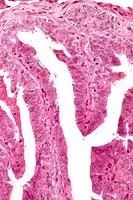

Intermed. mag. Very high mag.

Very high mag.